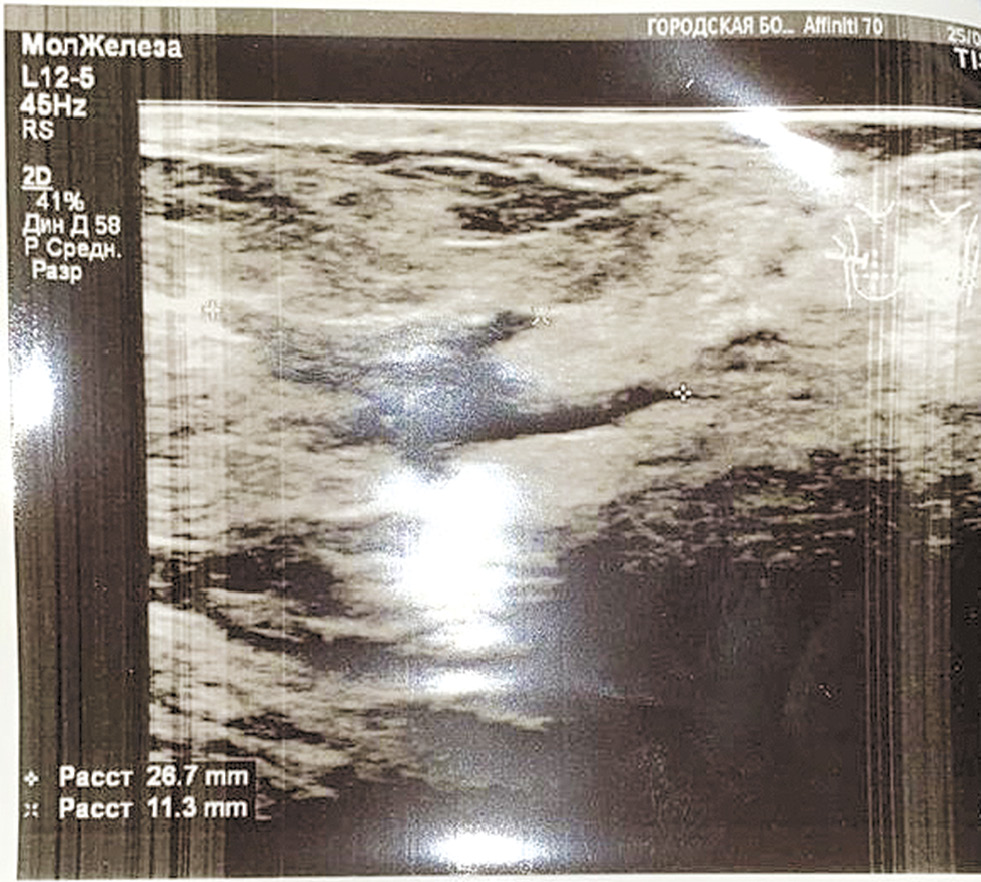

Осмотр во II фазу МЦ. Железистая ткань выражена, средней эхогенности, неоднородная за счёт жировых включений. Диффузно лоцируется большое количество гипоэхогенных трубчатых структур, сливающихся между собой.

Жировая ткань слабо выражена, неоднородна.

Млечные пути не расширены.

Очаговые изменения: не выражены.

Правая молочная железа после оперативного лечения. В проекции послеоперационного рубца лоцируется гипоэхогенный участок, с нечёткими неровными контурами, размерами около 27х11 мм.

Подмышечные лимфатические узлы:

справа: 20х7 мм, в инволюции.

слева: 17х7 мм, в инволюции.

Заключение: «УЗИ признаки диффузной железистой гиперплазии. Состояние после оперативного лечения правой молочной железы. Рубцовая деформация ткани правой молочной железы» (рис. 2).

Рис. 2. УЗИ молочной железы / Fig. 2. Patient's breast ultrasound